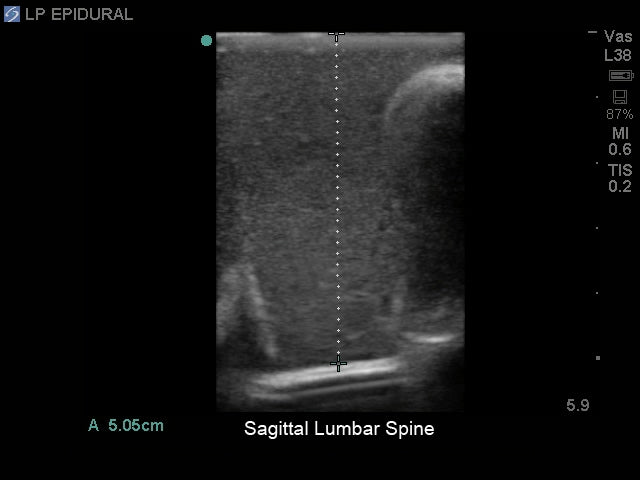

- Ultrasound can be used to identify the optimal insertion points, the angle of needle insertion, and determine the depth to the ligamentum flavum, epidural space, and spine

- Excellent ultrasound imaging properties

- Use any ultrasound system and never have to adjust system settings unrealistically or have trouble imaging the model's anatomy

- Ultra-durable self-healing tissue is extremely realistic in ultrasound imaging properties and feels like real human tissue